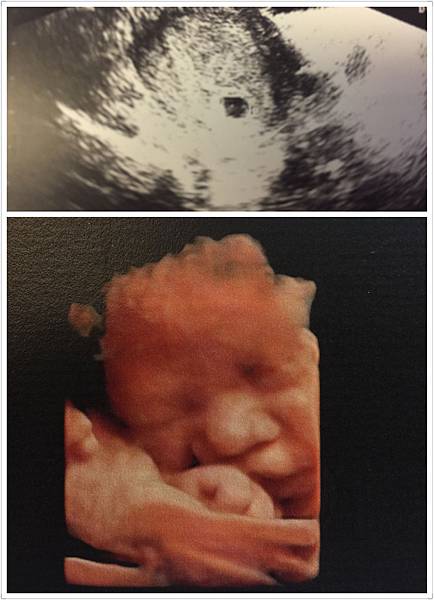

我從中期產檢之後都在木生婦幼診所,會選擇這裡是因為李木生醫生他超~級~有~名~,尤其是剖腹,之前聽很多人說 李醫生超細心又技術高超,還會把傷口處理得又好又美 (這點對愛漂亮的我來說好重要! 哈~ ) 很多我的好姊妹、同事 (&女明星) 都選擇在這生產,第一次進去以為到了藝廊,整個設計不大像醫院,整棟的建築有獨立電梯,婦產科、小兒科、病房、月子中心,跟其他婦產科不一樣的是,這裡除了掛號費 $250,每次照超音波要自費 $700,不過 4D真的看超清楚,超音波照片我都好好珍藏著,還有電子檔可留存,醫生說這台機器是最新技術。 上面是大寶的第一張照片,那天剛好體檢驗到,是一顆小胚胎!

上面是大寶的第一張照片,那天剛好體檢驗到,是一顆小胚胎!

下面是 36周在李木生拍 4D超音波照,超清楚吧! 寶寶正要吃手 哈~ (第一胎2015年) 這是之前我因腎盂腎炎住院期間 懷孕24周在馬偕照的,是不是從媽媽角度看起來有點難懂 哈~

這是之前我因腎盂腎炎住院期間 懷孕24周在馬偕照的,是不是從媽媽角度看起來有點難懂 哈~